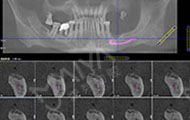

拍摄了CT,牙齿哪个地方有问题,看的很清楚,非常科学。但是口内有牙周病,需要先治疗再进行种牙,而且他们服务特别好,等待的时候还给倒水,安抚我让我感到很亲切,做了口内全口洁牙+喷砂+抛光+上药去除牙结石,是两个护士给洗的牙,一个细节就能提现这个机构好不好,卫生、环境方面都很不错,我也希望可以早点治疗好,做种植牙!